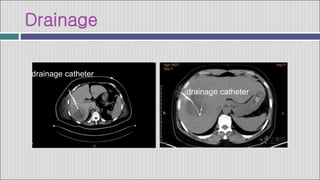

Drainage

drainage catheter

 Aspiration and placement of a drainage catheter under ultrasound

or CT guidance is beneficial for only a minority of pyogenic

abscesses, because most are quite viscous and drainage is

ineffective.

 Aspiration and IV antibiotic therapy can be expected to be effective

in 80 to 90% of patients.